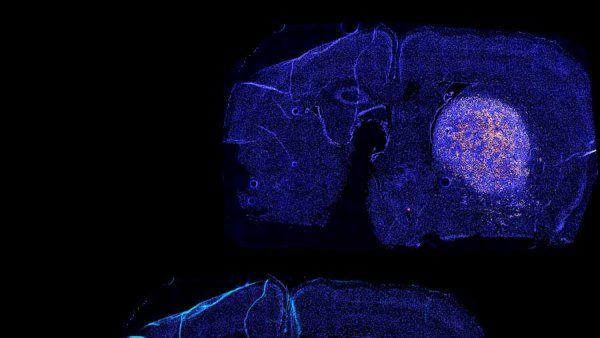

Novel Immunotherapy Combination Destroys Colorectal Liver Metastases